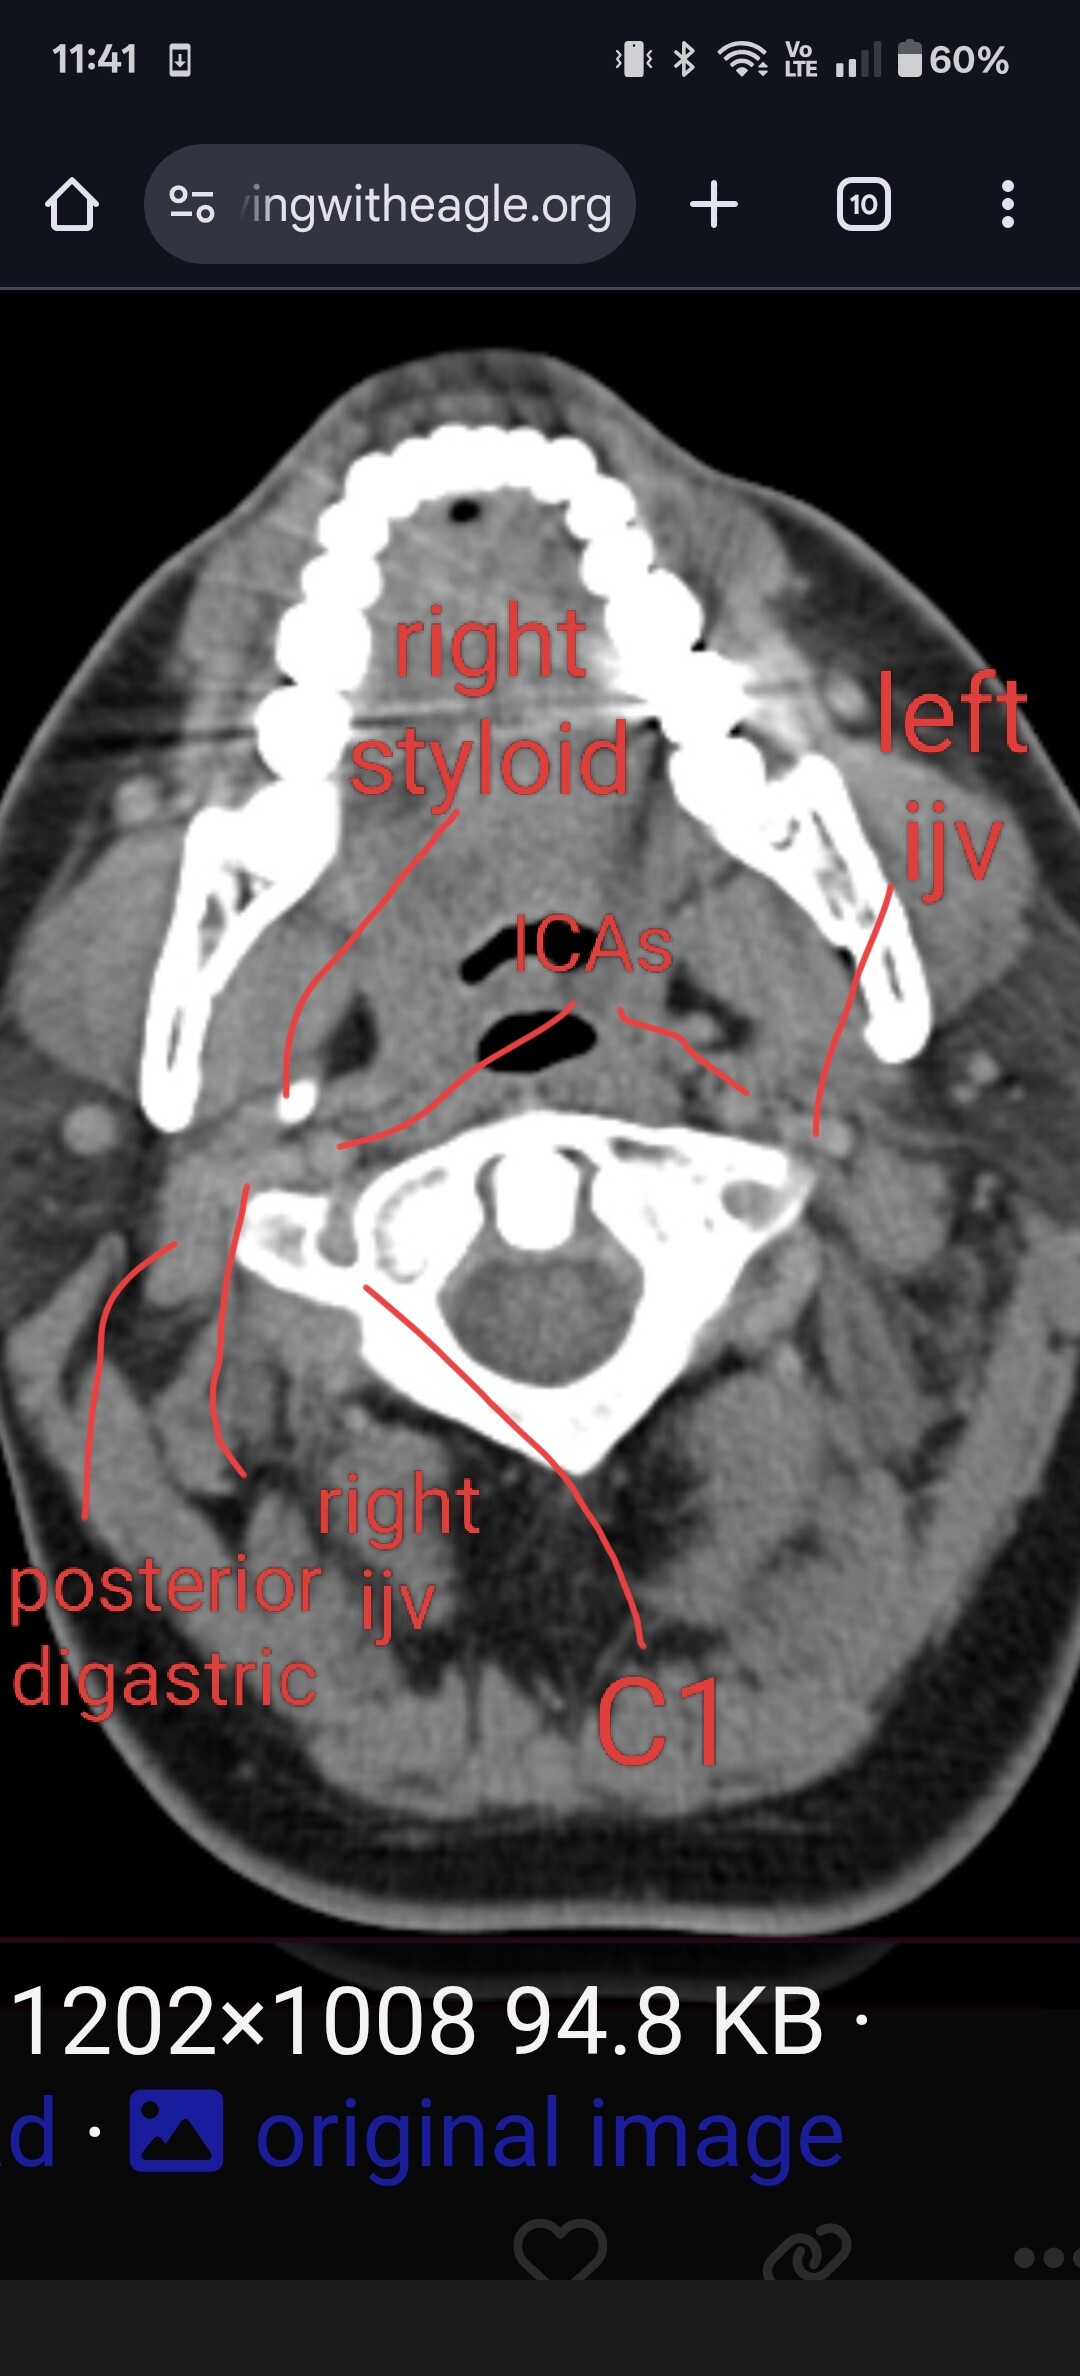

Typically, in the context of vascular ES, the most relevant view is of C1 in the axial view. I’ve attached my own imaging to help you know what to look for. It’s the top vertebrae with a white circle in the top middle:

@jalexy12 see attached annotated imaging.

It’s hard to see, but I believe your your right IJV is wedged between your posterior digastric and C1. The right styloid is not in contact with anything, at least at this level.

Left IJV appears to have some compression against C1. Left styloid is not present at this level.